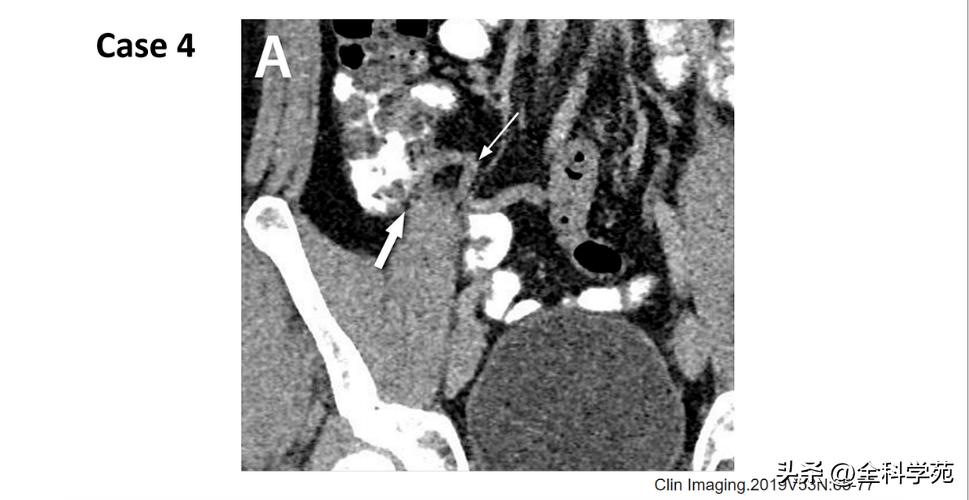

◆ 肠系膜淋巴结

>5 mm,周围伴有肠系膜炎症性改变

◆ 小肠梗阻 (Small bowel obstruction)